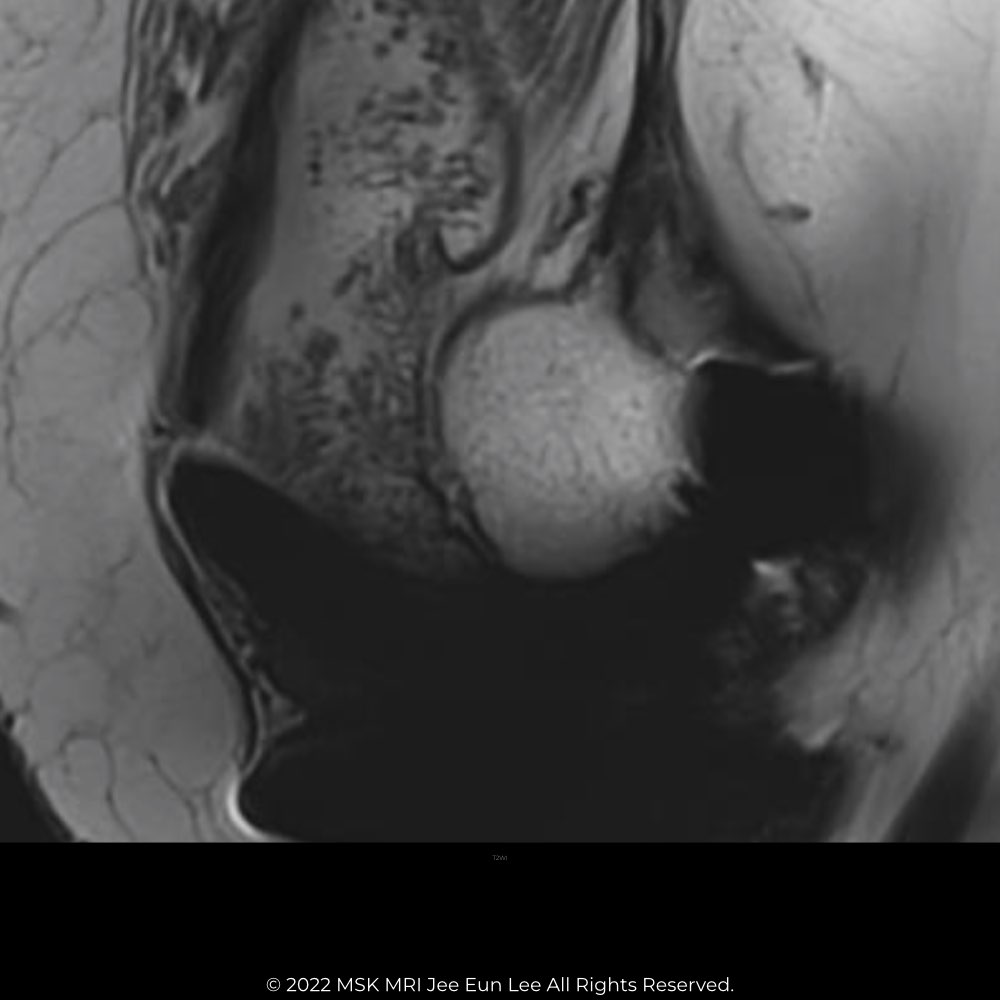

| MRI findings of Polyethylene Wear | ||

| Polyethylene wear–induced synovitis (61) (60) | Greater synovial proliferation observed on MRI corresponds with increased polyethylene wear. Frondlike synovial proliferation, thickened synovium, and intra-articular debris are seen. |